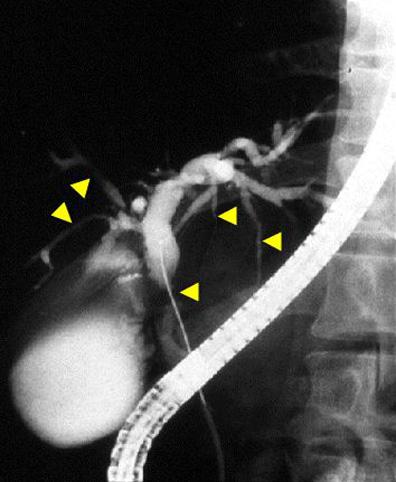

A case of ulcerative colitis associated with colon cancer and primary sclerosing cholangitis.

Inflammatory or ulcerative disease / lesions/Ulcerative colitis

X-ray